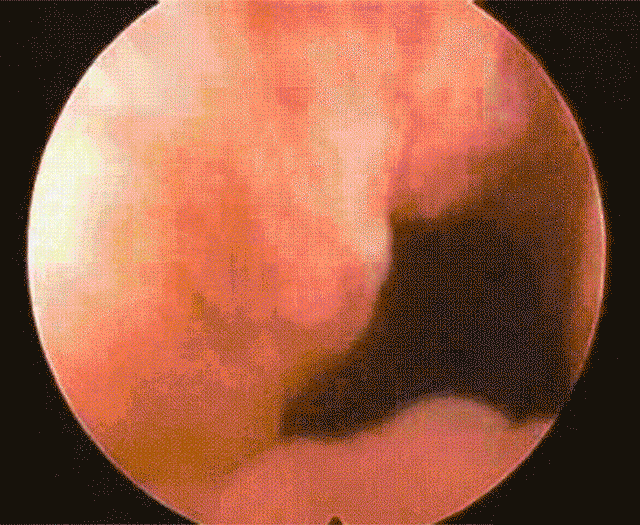

利用硬鏡與腹腔鏡的聯合應用,定位結石的數量、大小、位置等

利用柔軟纖細的膽囊鏡對膽囊內進行清查,確保不會出現結石殘留